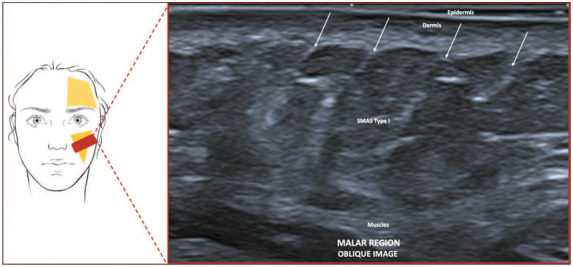

The superficial musculoaponeurotic system (SMAS) is a complex fibrous network connecting facial muscles to the dermis, with varying morphological characteristics across different facial regions. Recent studies have identified five distinct types of SMAS morphology, highlighting the need for region-specific interventions in facial rejuvenation. This pictorial essay explores ultrasound imaging of the SMAS using ultra-high frequency (24-33 MHz) probes, known as U-SMAS. Analysis of 186 full-face U-SMAS scans revealed consistent patterns in the facial and neck layers, with regional variations aligning with the Sandulescu classifications: type I (preparotideal); type II (chin and lip); type III (eyelid); type IV (temporal and parotideal); and type V (cervical). Understanding these morphological differences is crucial for accurate interpretation of ultrasound images and for optimizing pre-procedural assessments to ensure that aesthetic treatments are safe and effective. Knowledge of the SMAS architecture enhances the ability to visualize facial and neck anatomy accurately, particularly through U-SMAS imaging, ensuring comprehensive patient care in rejuvenation procedures.